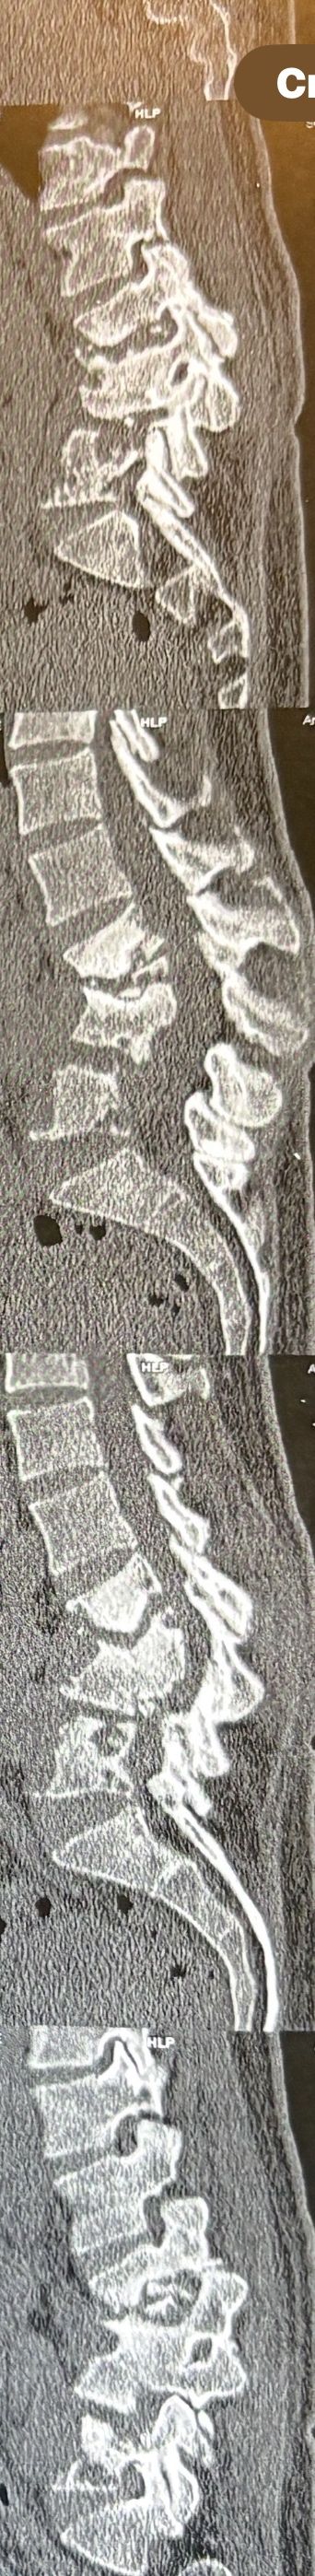

Few weeks ago I posted a case with an old TB spondylitis and listhesis with old fractures and severe canal stenosis (in her lower lumbar). A neurosurgeon who works with us at my clinic saw her in the second session

I attached her CT scan. Her PPD which was positive 2 months ago now it’s less than 3 mm. Since this patient has just low back pain and no radicular pain and can walk easily our neurosurgeon suggested no surgery and we emphasized that she has to complete her medication and be under her infectious diseases specialist

And if other signs and symptoms develops have to see surgeon again

42 years old female presented to my clinic yesterday on May15/2025 with chronic Low back for 2 yrs. She is from afghanestan and arrived to tehran 3 month ago. Visited pain specialist 3 months ago who just did PPD test and gave her Anti TB medication. In examination just had severe focal khyphosis from L3 to L5 without any tenderness. Her mri was done 2 months ago. Report is in Farsi and mentions of paraspinal puss/ fluid collection esp in psoas muscles, with extension of fluid collection to R pelvic region. Had 2 site of severe canal stenosis due to previous fractures of L3,4,5 and movement of fractured bones to the canal with complete distractions of those levels discs with fusion of L3 to L5

I ordered C T scan of lumbar and pelvic MRI / chest x r and reffered her to neurosurgon and infectious disease specialist to get full assessment and possible hospitalized for biopsy and surgery

As you know doctors of chiropractic would never. give treatment to patients with spinal Discitis/ osteomyelitis/ metastasis/ fracture( absolute chiropractic contraindications for treatment)